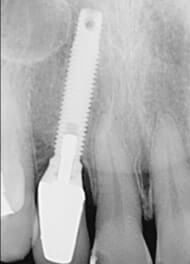

痛み止めの麻酔をして、あごの骨にインプラント(人工の歯根)を埋め込みます。手術に対して恐怖心がある方や全身状態に不安がある方では鎮静下(半分寝ている状態)で手術が受けられます。手術後は、通常、すぐにインプラントは使えません。骨とインプラントが結合するまで数ヵ月待ちます。 |